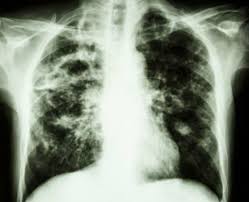

Alpha particles and beta particles are example of particulate radiation while cathode rays are beams of electrons in a partially evacuated glass tube with a potential difference between an. Our online radiology trivia quizzes can be adapted to suit your requirements for taking some of the top radiology quizzes. First, you need to identify the fractures inside the body. May 21, 2018 · radiology questions and answers (q&a) what is an example of particulate radiation? Dec 05, 2017 · more radiology quizzes oral radiology examination practice test! This quiz will test the dental student's understanding and knowledge of radiation physics and the fundamentals of radiographic interpretation. Apr 06, 2021 · a comprehensive database of more than 14 radiology quizzes online, test your knowledge with radiology quiz questions. Next, you need to diagnose the underlying condition.

First, you need to identify the fractures inside the body.